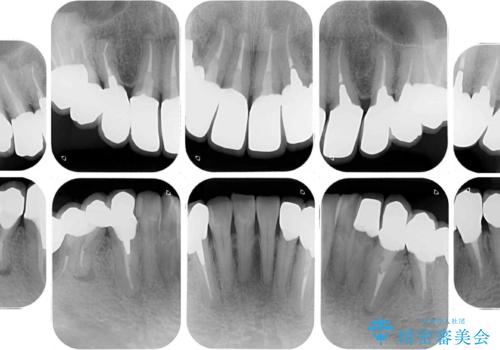

- 近医にて古いかぶせ物をセラミッククラウンにしようと治療を開始したものの、仮歯での咬み合わせが不安定とのことで、転院を希望して来院された患者様です。

骨格的に下顎骨が前方位に位置しており、上下前歯部の先端同士が接触する切端咬合でした。

このような方は咬み合わせが大きく変わると不安定となるため、まずは装着されている仮歯で咬合調整を行い、安定した咬み合わせとした後に、新しい仮歯に置き換え、その後オールセラミッククラウンにて補綴治療を行うこととしました。

仮歯で咬み合わせの調整を行ってからは、特に不安定になることもなく、非常にスムーズに治療を進めて行くことができました。